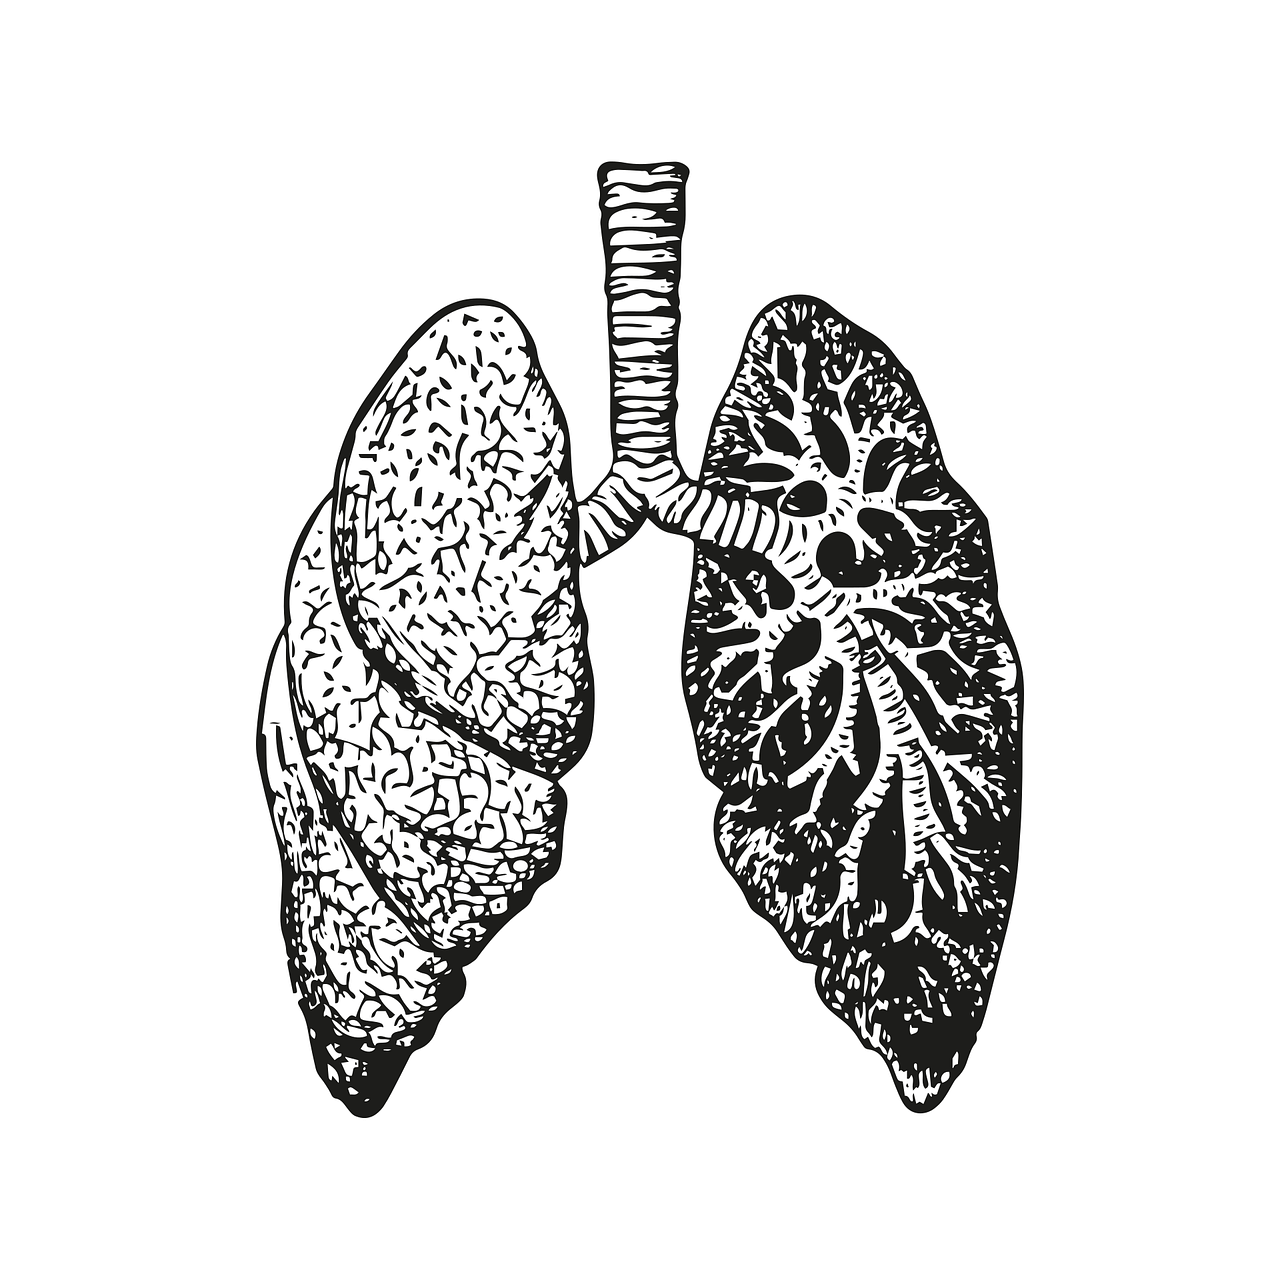

결핵은 폐, 신장, 신경, 뼈 등 우리 몸속 거의 대부분의 조직이나 장기에서 병을 일으킬 수 있으며 그중에서도 결핵균이 폐 조직에 감염을 일으키는 폐결핵이 대부분을 차지합니다.

결핵은 일반적으로 항결핵제만 꾸준히 잘 복용하면 완치가 가능한 질환이지만, 완치의 여부와 무관하게 결핵에 의해 감염된 폐에는 다양한 형태로 그 후유증이 남게 됩니다.

이는 폐실 질에서부터 흉곽에 이르기까지 전체 흉부 어디에도 가능하며 석회화된 결핵종, 폐 실질 내 공동, 기관지 확장증, 라스무센(Rasmussen) 동맥류, 기관지 흉막루, 기흉 등이 있습니다.